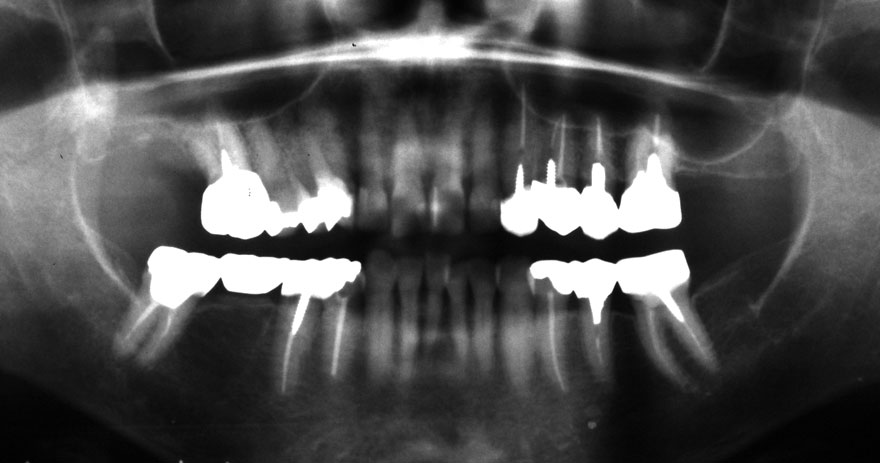

開始年齢 40代

初診時 40歳 女性 平均歯槽骨喪失量:3.14mm

32年後 72歳

平均歯槽骨喪失量:3.22mm

32年間喪失量:-0.08mm

年間喪失速度:-0.002mm

(ケア頻度:1.86ヵ月ごと)